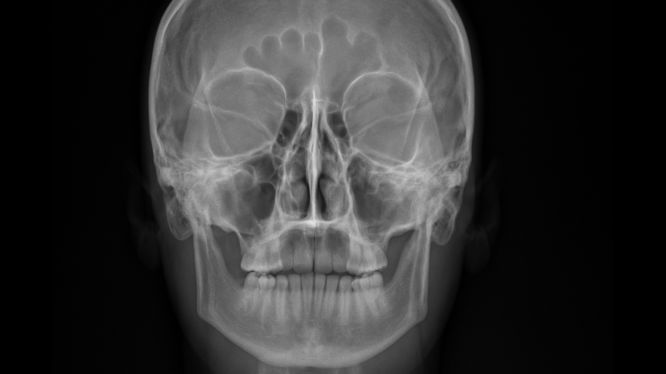

También conocida como proyección Caldwell o radiografía PA (posteroanterior), la radiografía Caldwell, , es una técnica radiológica en la que el paciente coloca la frente y la nariz sobre la placa, permitiendo obtener una imagen frontal del cráneo y la cara.

De este modo, esta posición particular permite que los rayos X entren desde atrás hacia adelante, produciendo una vista excepcionalmente útil de:

- 🌀 Senos frontales

- 👁 Órbitas (cavidades oculares)

- 😶 Estructuras faciales superiores

- 🦴 Huesos nasales

- 🦷 Zonas relacionadas con la odontología y la articulación temporomandibular (ATM)

🔍 ¿Qué estructuras permite ver la proyección Caldwell?

Esta es una de las razones por las que la radiografía Caldwell es tan solicitada: ofrece una vista clara, simétrica y muy diagnóstica de zonas que pueden pasar desapercibidas en otros estudios.